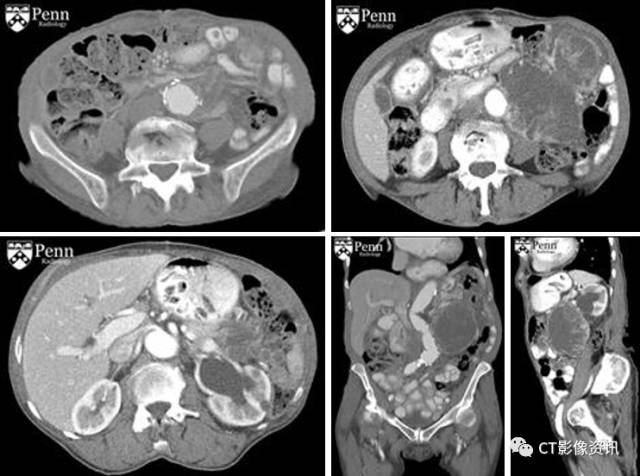

病史 女性85岁,腹主动脉瘤破裂修补术病史,现发现腹部肿块,进行性增大伴腹部锐痛,其血流动力学稳定,但血象示重度贫血。

CT增强如下图所示: